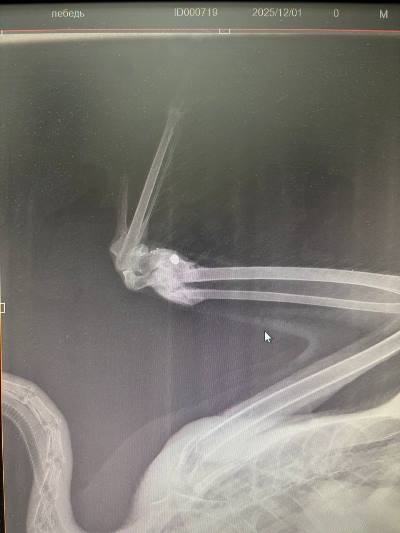

Ветеринары осмотрели птицу и сделали рентген. Это позволило диагностировать мелкооскольчатый перелом локтевой и лучевой костей крыла. Предварительно лебедя подстрелили.